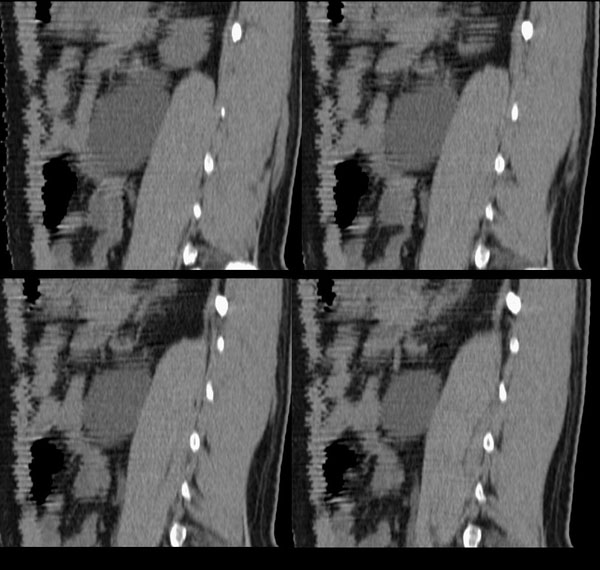

m29y平常体健,无明显不适。单位体检时发现左肾区病变。来我院作ct如下(病人不做增强):

左侧输尿管冠、矢状重建: